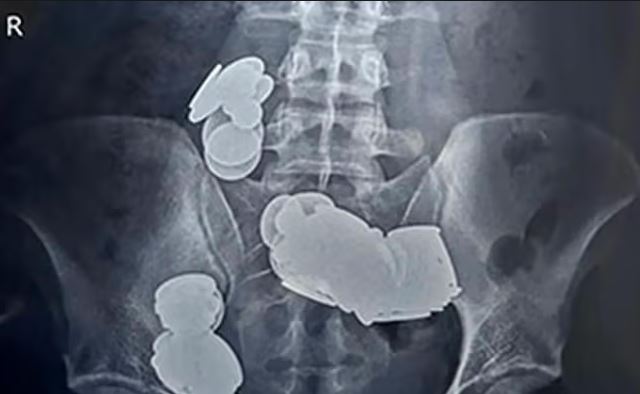

Indijac (26) je vjerovatno brzo požalio zbog svoje besmislene ideje. Kako bi brže došao u top formu, muškarac iz Delhija progutao je čak 39 novčića i 37 magneta. Ali imao je krajnje neobičan razlog za svoj postupak. Naime, bio je uvjeren da će mu cink u novčićima pomoći u bodibildingu.

Ali posljedice su bile katastrofalne. Mladi Indijac je dobio jake bolove u stomaku i nekoliko puta je povratio. Zbog toga je pomoć potražio u bolnici, gdje je uslikan rendgenskim snimkom, prenosi oe24. Ono što su ljekari vidjeli zaprepastilo ih je.

Novčići su se zalijepili zajedno zbog magnetske sile, što je dovelo do crijevne opstrukcije. Ali 26-godišnjak je imao izuzetnu sreću, jer su hirurzi uspjeli da uklone sve novčiće i magnete, a pacijent je nakon sedmicu dana mogao da napusti bolnicu.